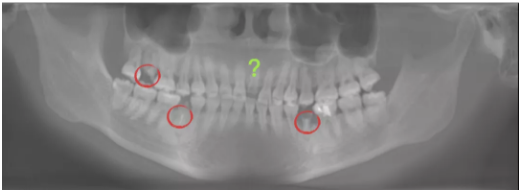

三、影像检查

— 残根17、35、45保留无望(修复间隙变窄)

—18智齿牙根情况尚可

—21斜面断端,唇侧断端位于龈下1mm,唇侧测根长12mm,腭侧测根长16mm